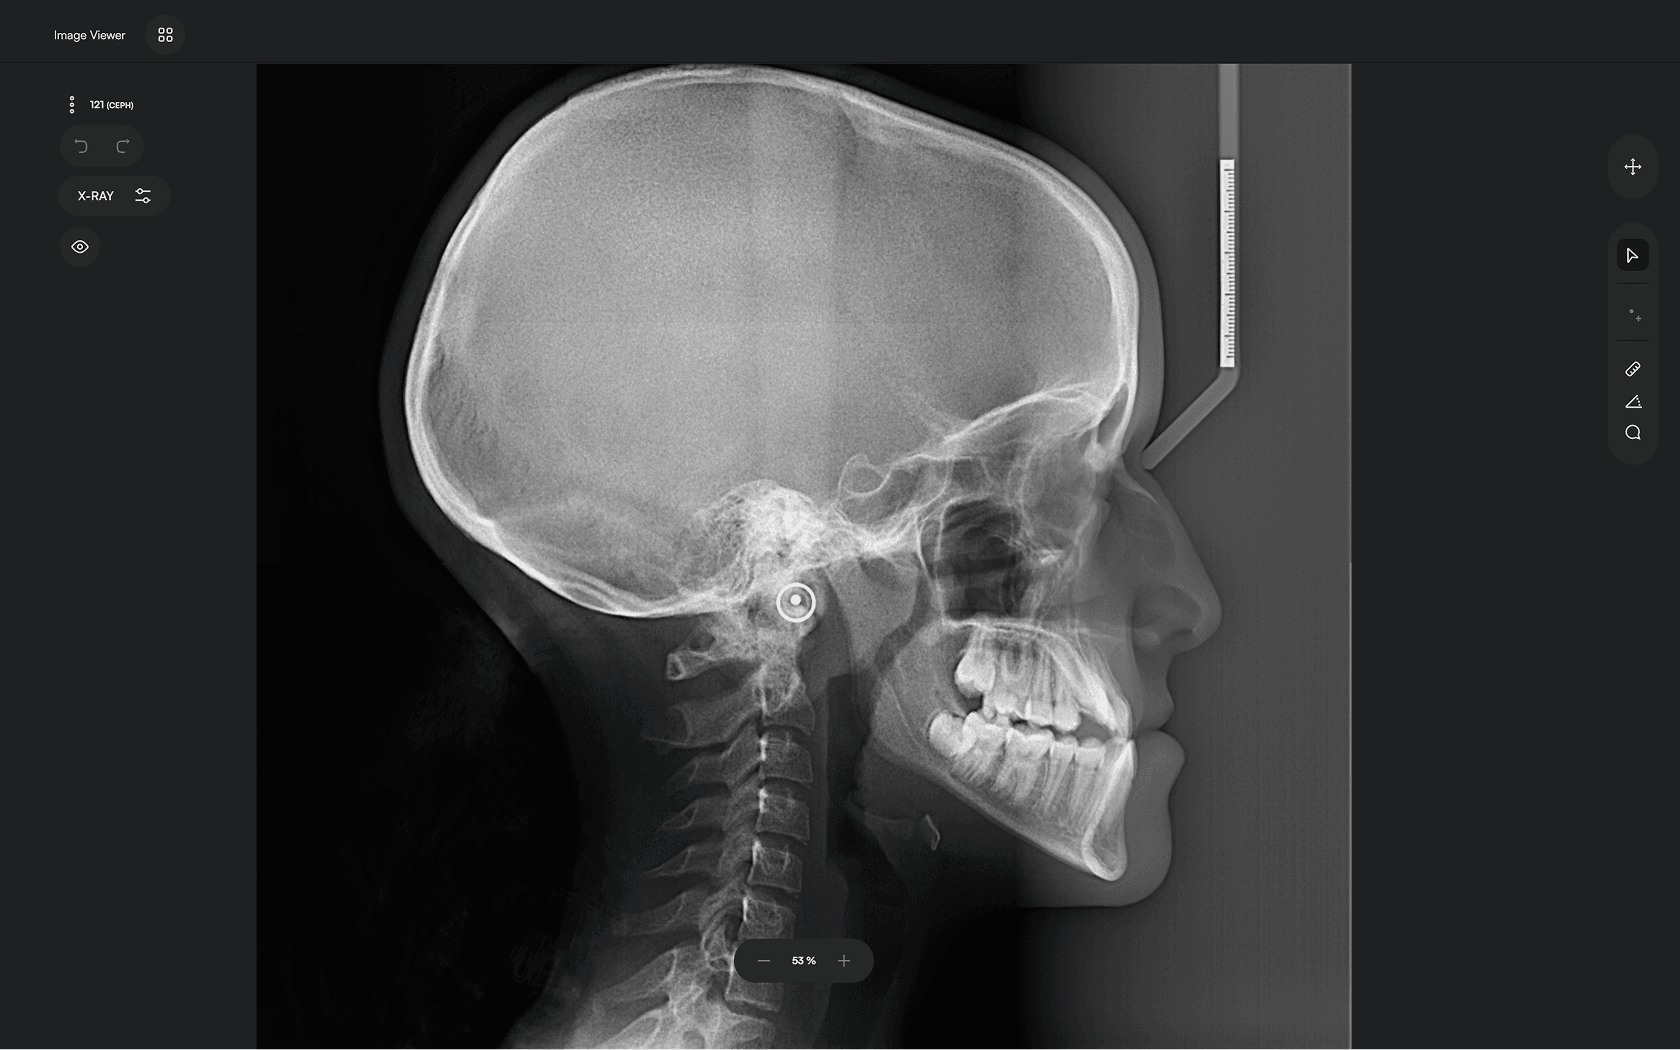

AI-driven Automated Lateral

Cephalometric Tracing

Upload X-ray

Upload your lateral cephalometric X-rays